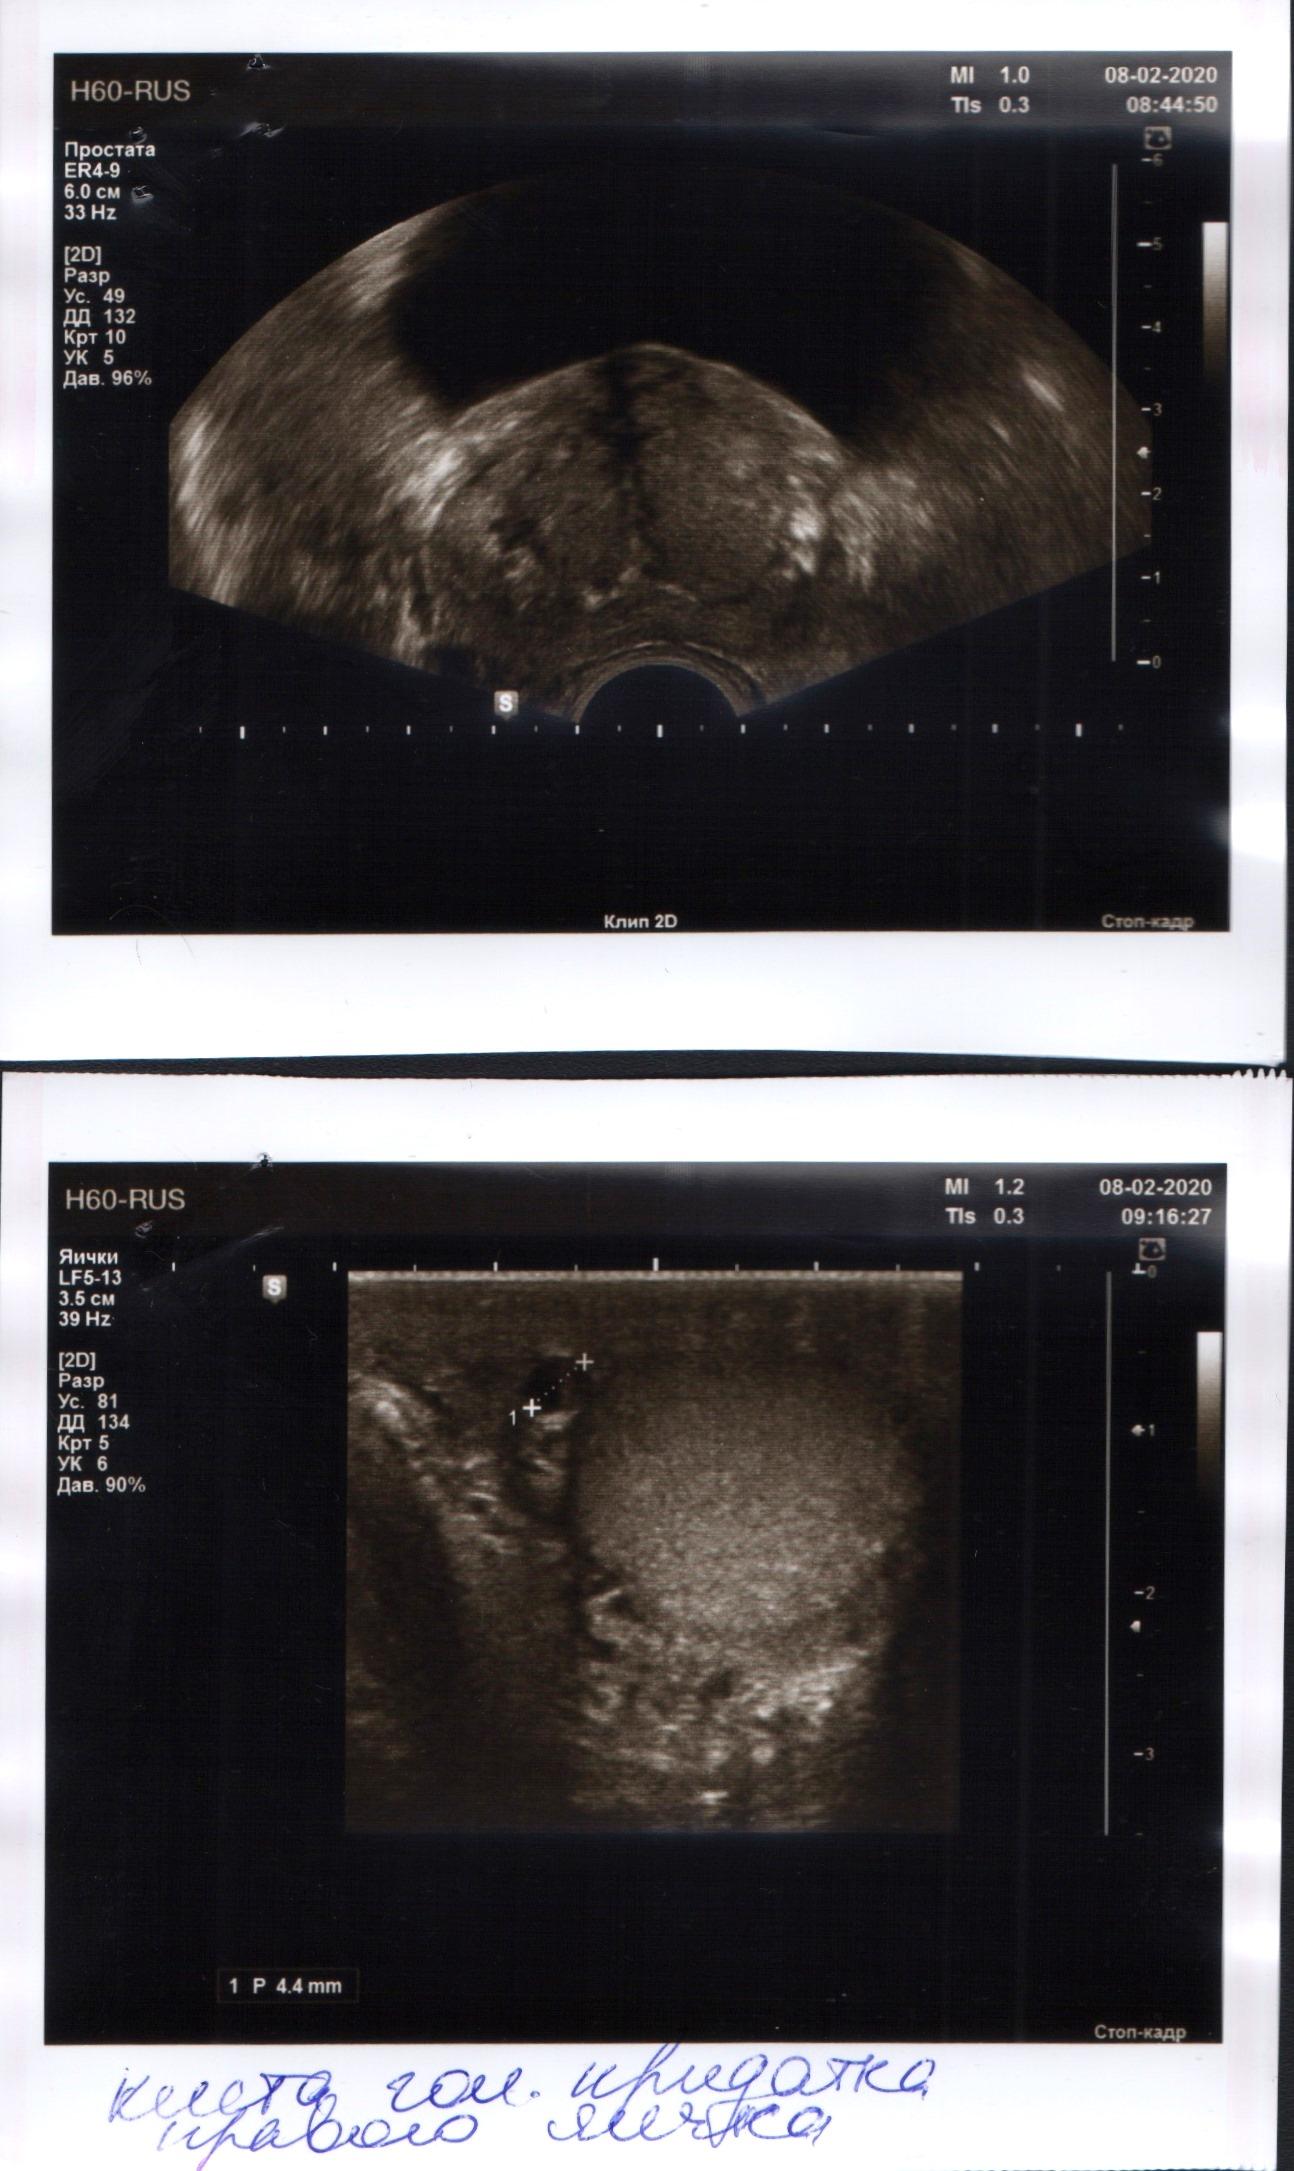

В 1989 г. в НИИ урологии мне удаляли камень в лев.почке. Почти тогда же обнаружили простатит и года два-три назад установили аденому предст.железы. Принимал аводарт, Омник, Даводарт. Мучает частая беготня "по-малому" ночью и вялая потенция. Хотелось бы совета. Спасибо

Здравствуйте! Нужно сдать анализ крови на ПСА. При нормальном результате можно обсудить с Вашим урологом применение дуодарта(который Вы принимали, судя по Вашему письму). Удачи!